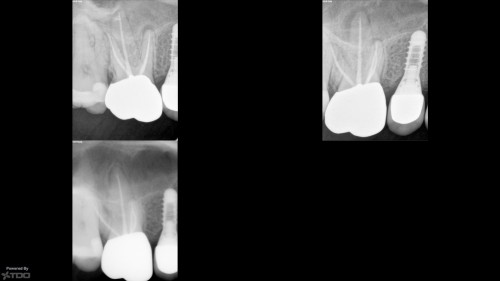

#18 RCT

#18 RCT With this kind of gingiva sinking the whole tooth an indirect post-endo would […]